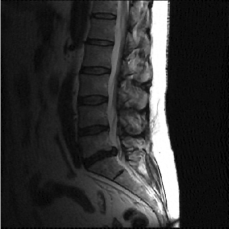

(d) Circle of Willis

Figure 2: Test Images.

We turn now to test TDIHT for high dimensional signals. We test the performance of several MRI images: the Shepp-Logan phantom, FLAIT brain image, T2 Sagittal view of the lumbar spine and the circle of Willis. The first image is of size 256×256256256256\times 256, while the other are of size 512×512512512512\times 512. They are all presented in Fig. 2.